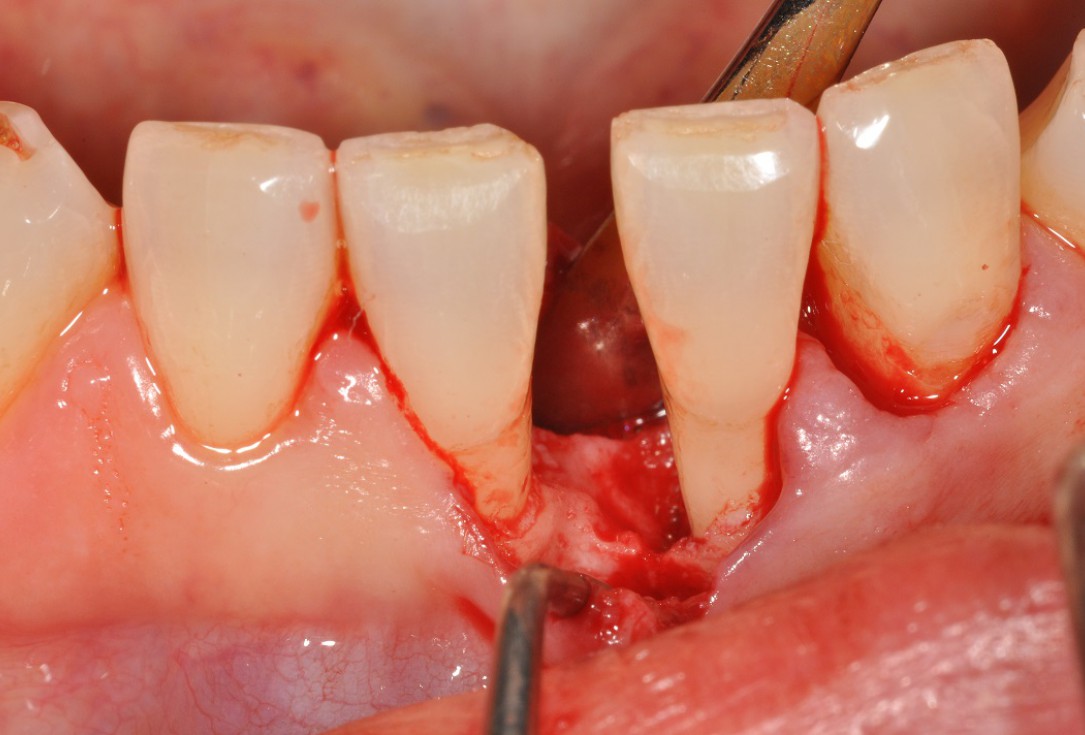

03/13 - Flap elevation and presentation of the defect.

Wide intrabony defect treated with the modified papilla preservation flap in conjunction with Straumann® Emdogain® and autogenous bone - Dr. B. Molnar